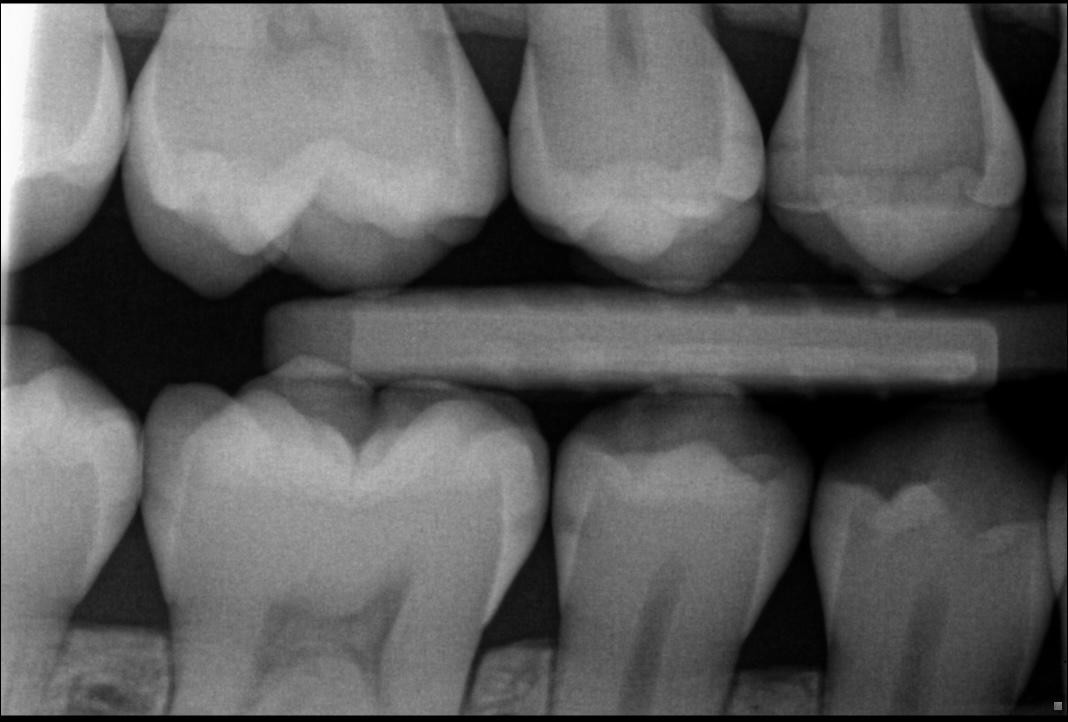

3. In the X ray bellow for which jaw periodontal bone loss is evident?